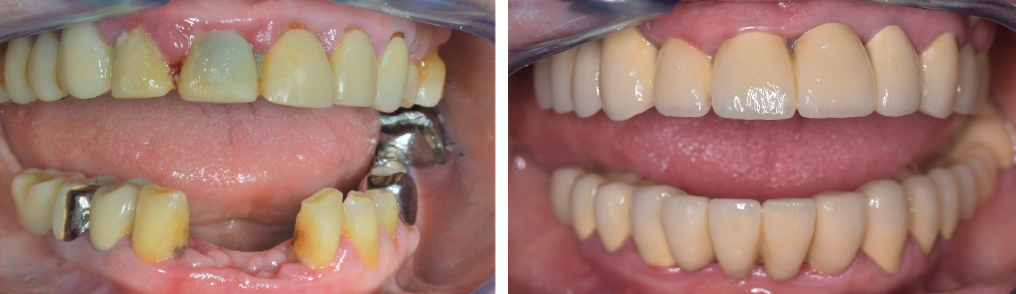

Pe termen lung, lucrurile în general evoluează foarte bine dacă se respectă detartrajele periodice la 4-6 luni, iar igiena personală este strictă și realizată cât se poate de atent. De asemenea se recomandă o atenție sporită, iar la primele semne de sângerare gingivală să fie programat un control. Chiar dacă boala parodontală nu se poate vindeca, ea poate fi stopată și ținută sub control printr-o igienă personală strictă, combinată cu igiena profesională periodică realizată la cabinet de către medicul dentist. Odată ce lucrurile se stabilizează, se va recomanda continuarea tratamentului cu reabilitarea protetică, pentru înlocuirea dinților absenți și îmbunătățirea atât funcțională cât și estetică.

În cazul din imagine (Fig. 5.3.4.), s-a realizat inițial tratamentul bolii parodontale, prin detartraje și surfasaje radiculare, asociat cu îmbunătățirea igienei personale. Ulterior, a urmat un tratament protetic fiind realizate coroane metalo-ceramice, ce au restabilit complet funcția masticatorie și estetică. Pacienta revine la cabinet periodic, la fiecare 4 luni, pentru control și igienizare.